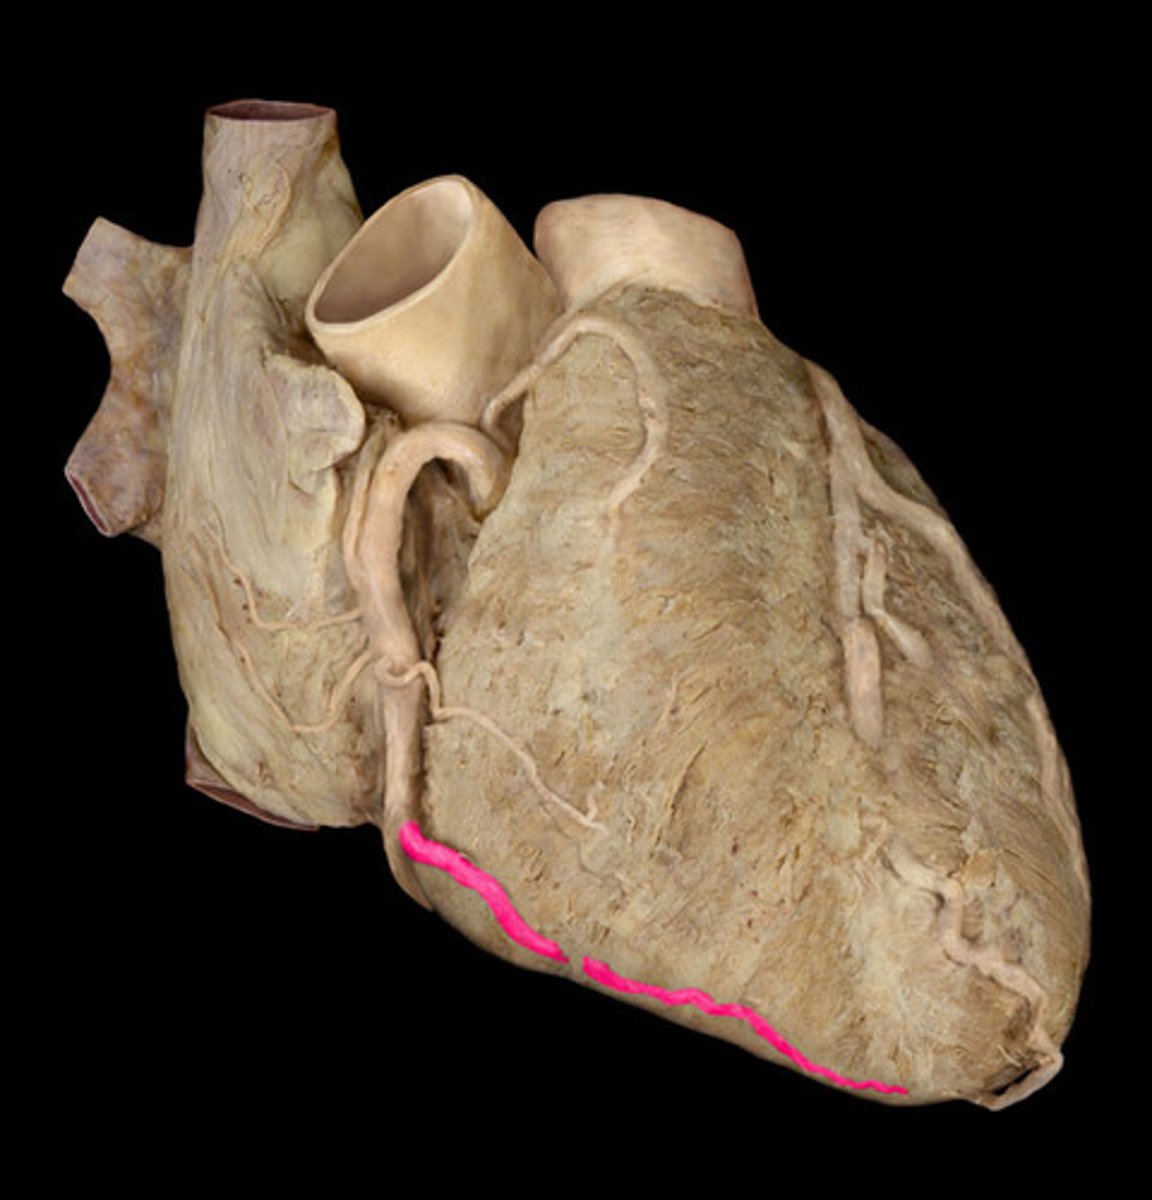

inferior boarded of the heart

horizontal, formed mainly by right ventricle (on x-ray)

small cardiac vein

anteriorly along the inferior border of the heart

right side of the 'T'